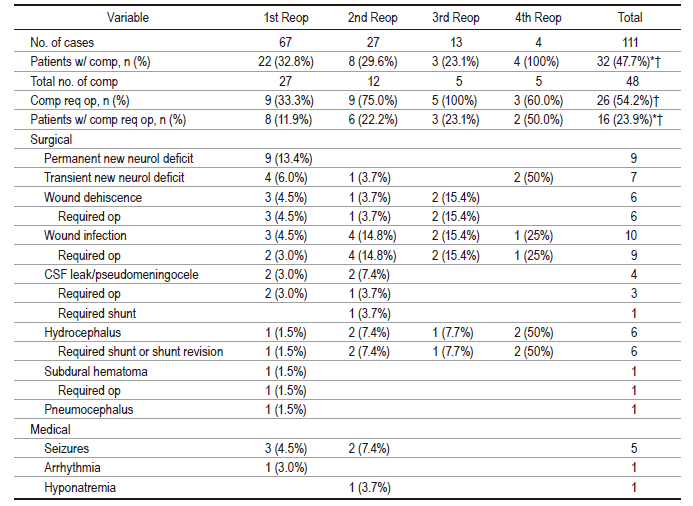

23. 复发非颅底脑膜瘤再次手术的疗效分析

Surgical outcomes after reoperation for recurrent non-skull base meningiomas.

Author: Stephen T. Magill, Cecilia L. Dalle Ore, Michael A. Diaz, Daara D. Jalili, David R. Raleigh, Manish K. Aghi, Philip V. Theodosopoulos and Michael W. McDermott

DOI: https://doi.org/10.3171/2018.6.JNS18118

复发脑膜瘤的主要治疗手段包括放射治疗或再次手术切除两种方法。而目前对于复发性脑膜瘤再次手术治疗的疗效及预后了解不足。鉴于现状,本文主要对复发性幕上非颅底脑膜瘤再次手术的预后进行回顾性分析,重点探讨导致术后并发症的危险因素。文章总共纳入67例已经接受过单次脑膜瘤切除的复发性幕上非颅底脑膜瘤患者,本研究过程中这些患者经历了111次再次开颅手术。患者中位年龄为53岁,女性占49%,中位随访时间为9.8年。再次入院最多见的症状是头痛,虚弱和癫痫发作。最后一次再次手术后的病理提示WHO等级为I级占22%,II级占51%,III级占27%。与患者初次手术相比,再次手术时肿瘤恶性程度变高的占22%。从肿瘤部位来看,有位于凸面(52%),矢状窦旁(33%),大脑镰旁(31%)和多发的(19%);其中52%的病例累及矢状面上中间三分之一。在总的111次再手术中,在32名患者身上发生了48次并发症(48%),其中26次(54%)并发症需要手术干预。没有围手术期死亡的患者。并发症主要包括神经功能缺损(总计14%,永久性8%),伤口裂开/感染(14%)和脑脊液漏/假性囊肿/脑积水(9%)。多因素分析结果显示,肿瘤累及矢状面中间三分之一(优势比 6.97,95% 置信区间1.5-32.0,p=0.006)和有认知功能改变的患者(优势比 20.7,95% 置信区间 2.3-182.7,p=0.001)与术后并发症的发生率显著相关。首次再次手术后的中位生存期的生存时间为11.5年,术后2年、5年和10年生存率分别为91.0%,68.8%和50.0%。研究表明复发性幕上非颅底脑膜瘤的再次手术术后并发症发生率较高。术前有认知功能改变或者肿瘤位于矢状面中间三分之一的患者是术后出现并发症的独立危险因素。作者最后指出:虽然对于复发脑膜瘤再次手术治疗可以提高患者的生存期。但是考虑到并发症的发生率,希望今后更多的基础研究能提供好的分子治疗手段。

图:复发脑膜瘤再次手术后并发症发生情况。